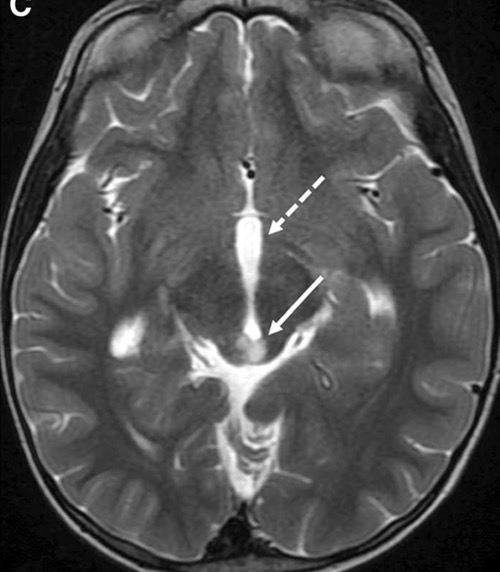

c. Lipomatose encéphalocraniocutanée (ECCL): peau, yeux, SNC)

ECCL: